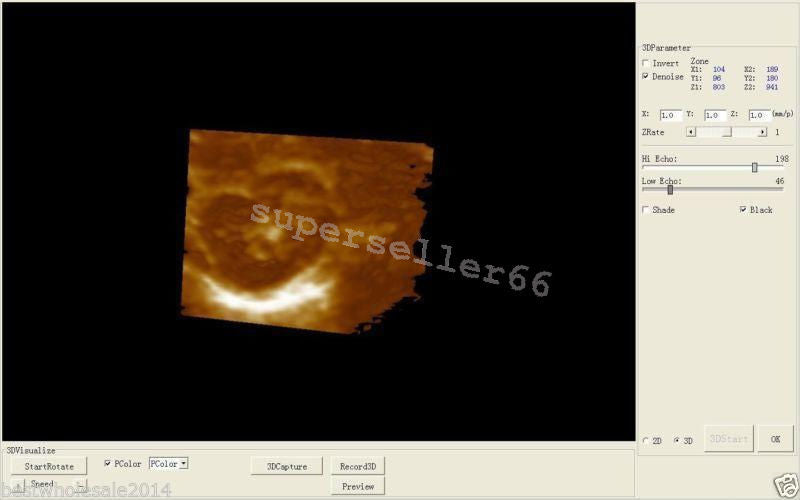

High-Resolution Display for Clear Imaging

The Ultrasound Scanner features a 10.1'' LCD screen that provides high-resolution images, ensuring that healthcare professionals can make accurate diagnoses. However, the clarity of ultrasound imaging is vital, because it directly impacts patient care. The intuitive interface makes it easy for users to navigate through various options, so they can focus on delivering quality healthcare.